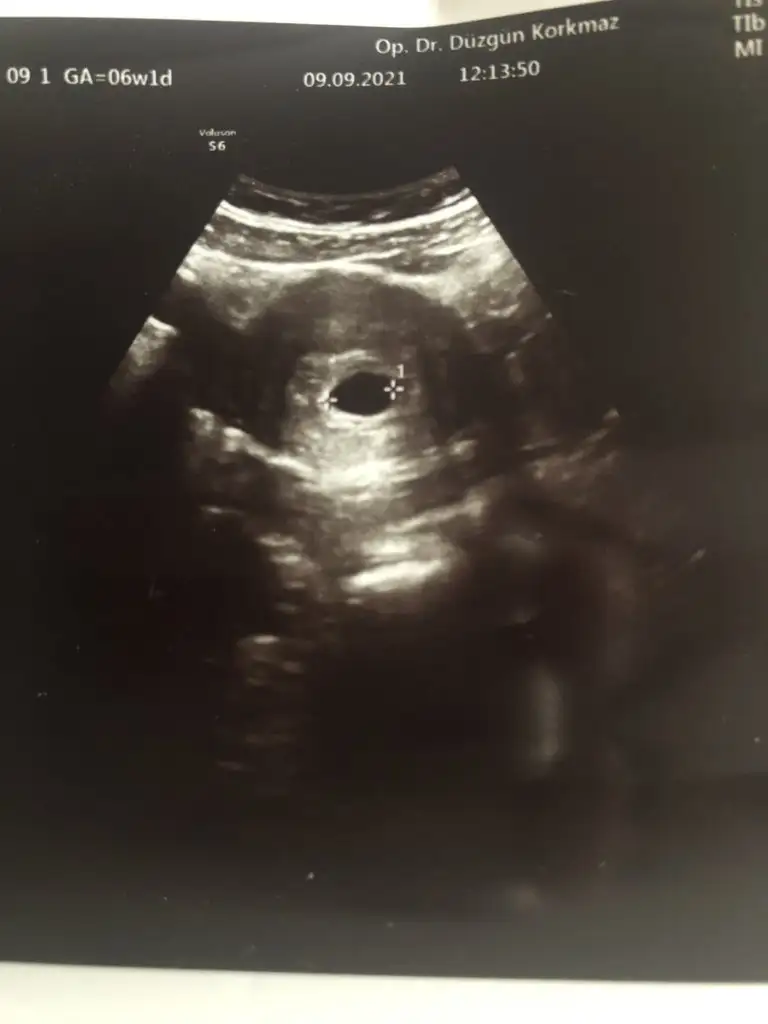

Benimki 6+1 bu şekilde canımKızlar 6+4 ve yakınlarında gidip ultrason görüntüsü aldıysanız bir paylaşabilir misiniz rica etsem

Teşekkür ederim Peki kalp atışı duymuş muydun bu ultrasonda?Benimki 6+1 bu şekilde canım

Canım bir de yanında bitane e daha kesemsi bir şey var o ne acabaEvet canım çok yüksek olmasada duymuştum. Ama bizim bebiş günüyle uyumlu gidiyor senin için perşembeden beri rahat değil istersen farklı bir doktora gidersen dinletir belki ya da gösterir ve için rahatlayabilir. İnsan ister istemez olumsuzu düşünüyor ama senin olumsuz düşüneceğin bir durum yok doktorunda daha erken demiş olumsuz birşey söylememiş güzel düşünelim güzel olsun

Ben pek bilmiyorum canım ama yolk kesesi olabilir belkiCanım bir de yanında bitane e daha kesemsi bir şey var o ne acaba